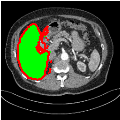

3.3 Results and Discussion

Our primary findings comparing the proposed model to baseline fully-supervised models when segmenting the liver from the LiTS dataset are reported in Table 1. The reported results demonstrate that our SAM-Mix model consistently achieves higher Dice scores compared to the fully supervised baselines as well as the two-stage SAM-PP method. Against U-Net, the best-performing fully supervised method, the SAM-Mix variant trained on 50 segmentation labeled slices (SAM-Mix-50), achieves a Dice score improvement of 5.9%. In terms of Hausdorff distance, while the fully-supervised baselines do slightly outperform SAM-Mix-5 and SAM-Mix-100, SAM-Mix-50 does achieve a lower Hausdorff distance by 22.38%. Qualitative evaluation as shown in Figs. 3 further affirms the superiority of SAM-Mix over baseline and existing fully-supervised methods as well as the two-stage SAM-PP variants. Furthermore, the boxplot visualization in Fig. 2 showcases consistently improved performance by SAM-Mix outperforming all the fully supervised and semi-supervised methods.

![]() |

| U-Net | nnU-Net | TransU-Net | SAM-PP-0 | SAM-PP-5 |

| SAM-PP-50 | SAM-PP-100 | SAM-Mix-5 | SAM-Mix-50 | SAM-Mix-100 |